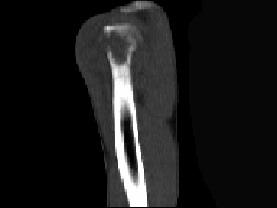

问题 患者,男,29岁,行走时不慎跌倒,曾拟为左肱骨头骨折并行固定,但半年后疼痛未减轻,触压局部骨质松软,如触及乒乓球感,明显叩击痛,请结合所提供图像,选择最佳答案 ( )

选项 A、骨转移瘤 B、骨结核 C、骨网状细胞肉瘤 D、左肱骨头骨折 E、化脓性骨髓炎

答案 C